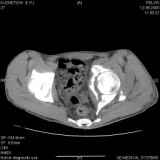

Уважаемые коллеги! Хотелось бы услышать совет по тактике лечения представлленого больного.Поступил после лечения в одном изотделений области. Травма 2,5 месяца назад. После выведенияиз шока был произведен остеосинтез перелома бедра, предплечья, до перевода к нам проводилосьвытяжение по оси шейки бедра за стержень, введенный в большой вертел. На сегодня деформацияригидна, клинически мобильности не определяется. Заранее признателен. P.S. Данный вид травм не включен в перечень "высокотехнологичных операций", направить длялечения по квотам Минздрава очень сложно.

Это обзорные и косые снимки

Привет, Леонид. Оскольчатый высокий двухколонный перелом в такие сроки трогать не надо, т.к. это про такие переломы сказано: "кто с ножом на Ж. пойдет тот в ней и останется...".